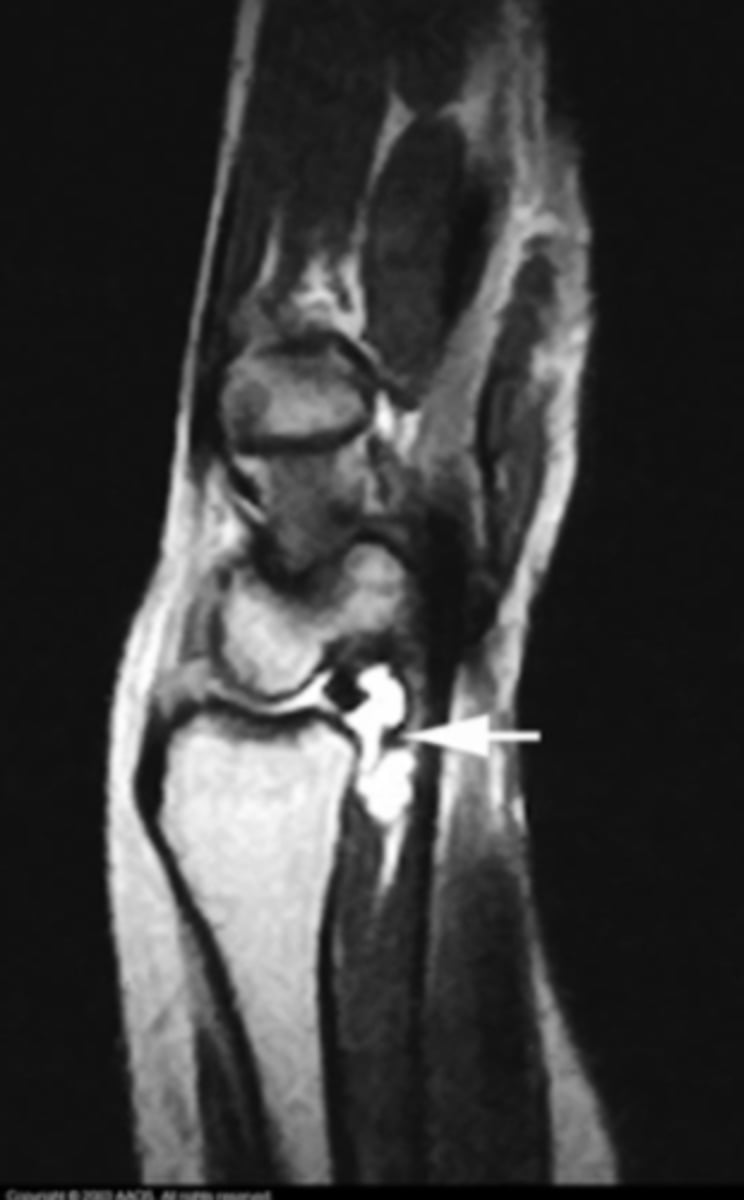

Ganglion cyst

What is the issue?